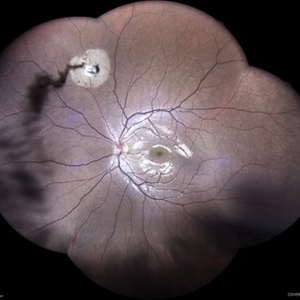

Familial Exudative Vitreo-retinopathy

Color photo montage of 21-year-old male with familial exudative vitreoretinopathy in an amblyopic eye.

Photographer: Dr. Akansha Sharma-Retina Foundation, Ahmedabad

Condition/keywords: familial exudative vitreoretinopathy (FEVR), retinal ischemia